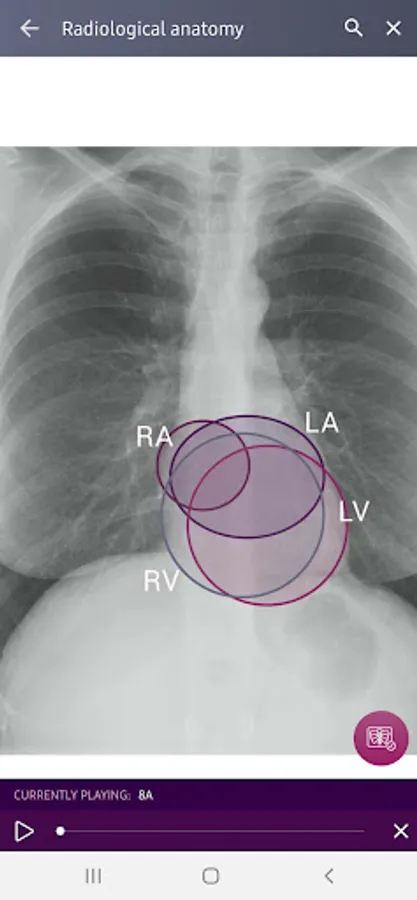

Radiological Anatomy – Descriptions of various anatomical structures as they would appear on PA and lateral chest x-rays.